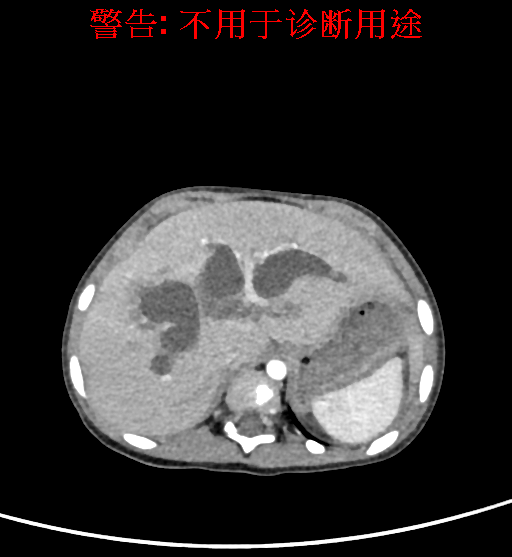

实验室检查: 血常规:血常规:WBC 11.49*109/L,NEU3.60*109/L,RBC4.36*1012/L,HB 119g/L, PLT 411*109/L,MCHC 318.0g/L, PCT 0.45%, RET% 1.64% 生化全套:ALT 18.00 U/L, AST 44.00 U/L, ALT/AST 0.41, ALB 47.35g/L,BIL-T 6.60 umol/L, BIT-D 2.68 umol/L, BUN 4.80 mmol/L, CREA 18.00 umol/L 肝炎全套: 炎症反应标志物: 诊疗过程: CT结果输入海信CAS系统后行3D重建及手术规划后,于2018-6-7全麻下行“胆囊切除+胆总管囊肿切除+肝总管空肠吻合术”手术治疗: 术前三维重建及手术方案设计: 将0.625mm双源薄层CT资料的静脉期和动脉期Dicom格式文件导入海信CAS系统。 通过调节窗宽窗位调整CT序号,对肝实质,胆囊,下腔静脉,肿瘤,肝动脉、门静脉及肝静脉等进行三维重建;系统自动计算肝脏体积,肝脏体积为383.8ml,通过术前模拟手术,精准判断手术切除范围,进行精密术前规划及讨论后实施手术。 手术步骤: 麻醉成功后,患儿取平卧位,2.5%碘伏消毒手术区皮肤,铺无菌巾单。取右上腹纵口长约5m,切开皮肤、皮下织组,腹直肌前鞘、腹直肌,后鞘和腹膜。探查见:胆总管3×2cm大小,胆囊管迂曲,长约10cm。剥离、切除胆囊,游离胆总管,将之横断:①近端即肝总管,剪裁后被吻合用;②远端游离切除囊肿内壁,直至胆总管开口于十二指肠处,冲洗后予以结扎缝扎。距treits韧带20cm处横断空肠:①近端与其远端25cm处的空肠侧壁行端侧双层吻合,吻合口通畅;②远端断端封闭,其侧壁剪开,并经横结肠后提至肝门处,与剪裁的肝总管行端侧双层吻合。缝合修补胆囊床及系膜裂孔,肝门部放置橡胶引流管一根。温盐水冲洗腹腔。检查无活动性出血,清点纱布器械无误,依次缝合腹壁各层。手术顺利,麻醉满意,出血不多,未输血,术后病人先进入麻醉恢复室,苏醒后回病房。手术时术者可开启Hisense CAS系统手势控制功能,对肝脏及胆囊解剖结构进行实时、全方观察、评估,起到术中导航作用。 术后病理: 1. (囊肿壁)囊肿性病变,囊壁构成于增生的纤维组织呈慢性炎,内衬假复层柱状上皮,囊壁内见较多增生的腺体。请结合临床。 2. 慢性胆囊炎。 随访情况: 患儿术后2周恢复良好 术前CT检查:动脉期

静脉期

平衡期